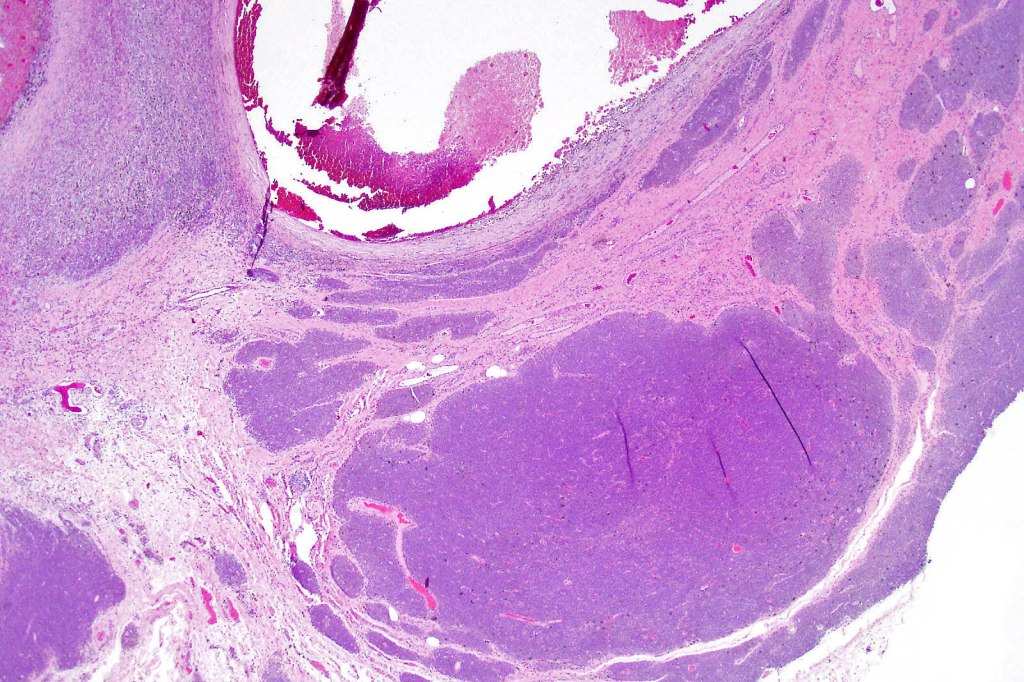

Histological features

•Most often are distinctive at scanning/low power examination due to the depth of involvement

•Hyperkeratosis, acanthosis and commonly papillomatosis

•Nested junctional component & nests within the papillary dermis

•Diffuse infiltrate of nevus cells often extending deeply into the dermis or beyond, single filing is often present at base & may involve the septa of the subcutaneous fat

•Involvement of appendages & arrector pili muscles

•Neurotization, neurofibroma-like lesions & neurocristic hamartoma

•Perineural sheath infiltration

•Blood vessel and lymphatic wall infiltration

•Superficial mitotic activity

This melanoma arose in a small congenital nevus of the scalp. It metastasized widely. Varying features in different fields.